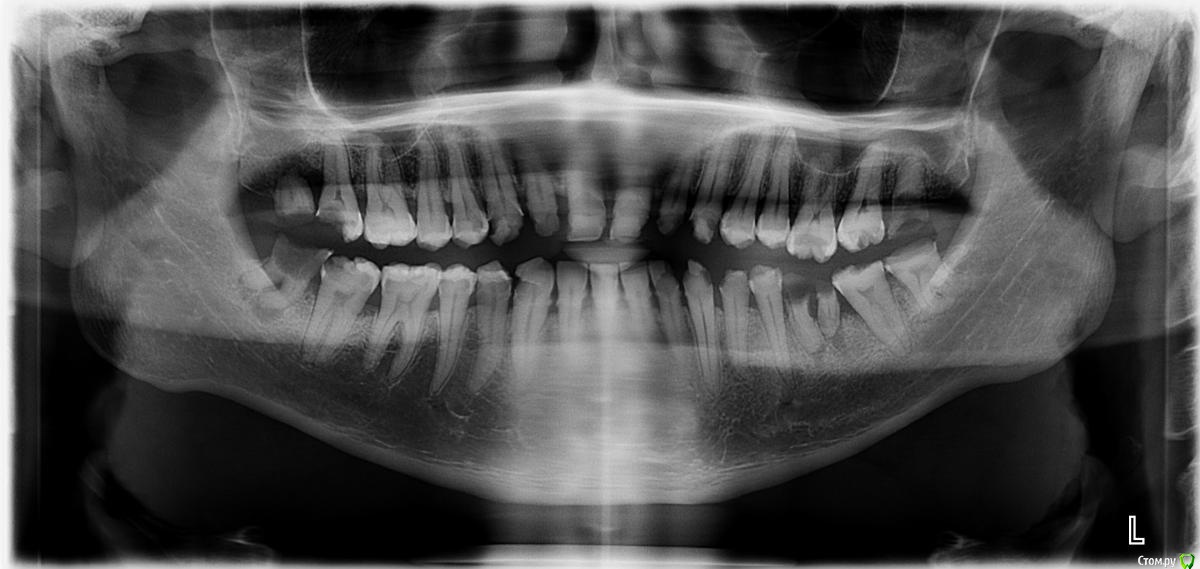

faity Опубликовано 27 июля, 2015 Поделиться Опубликовано 27 июля, 2015 (изменено) 1.8, 1.7, 2.8, 3.8, 3.6, 4.8 под снос, имплантация и тоталтотал можно оверлеем без девитализации ЕМах на все зубы, кроме 3.1, 4.1, 4.2, на них виниры Изменено 27 июля, 2015 пользователем faity 1 Ссылка на комментарий

Doc.IQ Опубликовано 27 июля, 2015 Поделиться Опубликовано 27 июля, 2015 100% чем то балуется..Ремотерапия в данном случае результатов не даст..произвести удаление 18,17,28,38,48,36,сделать некрэктомию оставшихся зубов,оценить полученный результат,после этого выбирать дизайн препаровки,ортопедическую конструкцию,материал..импланты само собой в дистальных отделах..кажется мне,что без кладок кое где будет не обойтись... Ссылка на комментарий

DmitrySH Опубликовано 29 июля, 2015 Поделиться Опубликовано 29 июля, 2015 1.8, 1.7, 2.8, 3.8, 3.6, 4.8 под снос, имплантация и тоталтотал можно оверлеем без девитализации ЕМах на все зубы, кроме 3.1, 4.1, 4.2, на них виниры Ну как сейчас можно планировать ортопедию, оверлеи или нет.???Сперва тут удаления и тотальная терапия, убрать все рыхлое, по показаниям где-то эндо. Где-то витальными оставлять, но без фанатизма. 1 Ссылка на комментарий